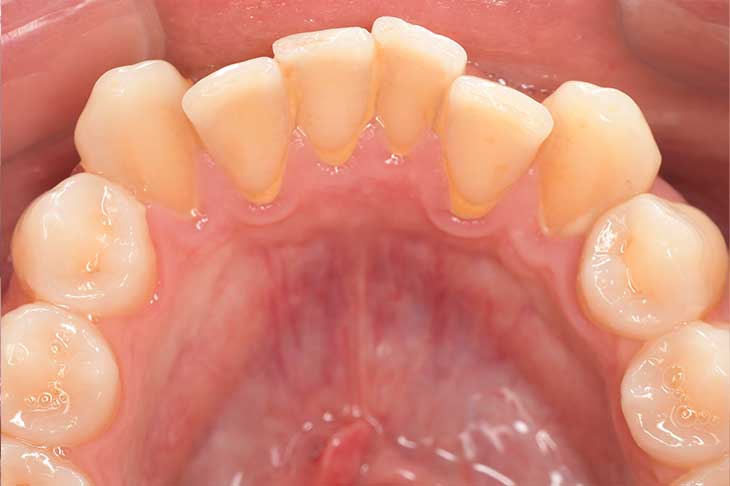

CASE 14

下顎before

下顎after

臼歯before

臼歯after

基本情報

| 年齢・性別 | 27歳・男性 |

| 主訴 | 歯石とりたい |

| 治療内容 | スケーリング |

| 治療期間 | 30分 |

| 治療費 | 約1,500円(保険診療) |

| リスク・副作用 | 知覚過敏、歯肉退縮、出血 |

| 治療方針 | 歯列不正でプラークがつきやすいため、TBIを行い定期的に歯石を除去していきます。 プラークコントロールが出来るようになったら定期検診でクリーニングを行っていきます。 |